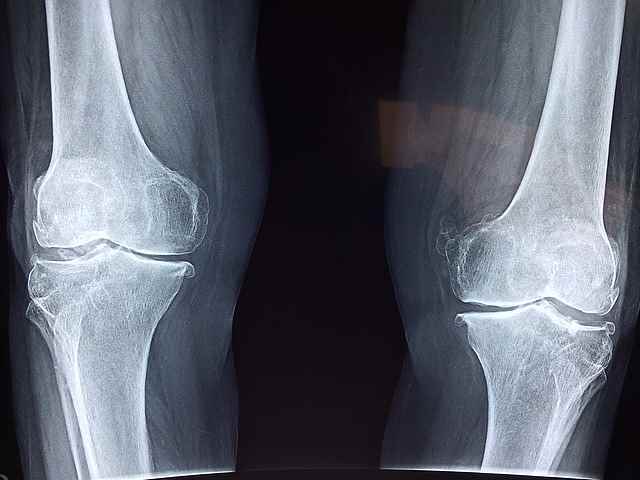

2. 골관절염

무릎 통증의 가장 흔한 원인 중 하나는 연골이 분해되는 것을 특징으로 하는 퇴행성 관절 질환인 골관절염입니다. 연골이 닳으면서 뼈가 서로 마찰되면서 무릎에 통증, 경직, 붓기 등이 생길 수 있습니다.

골관절염